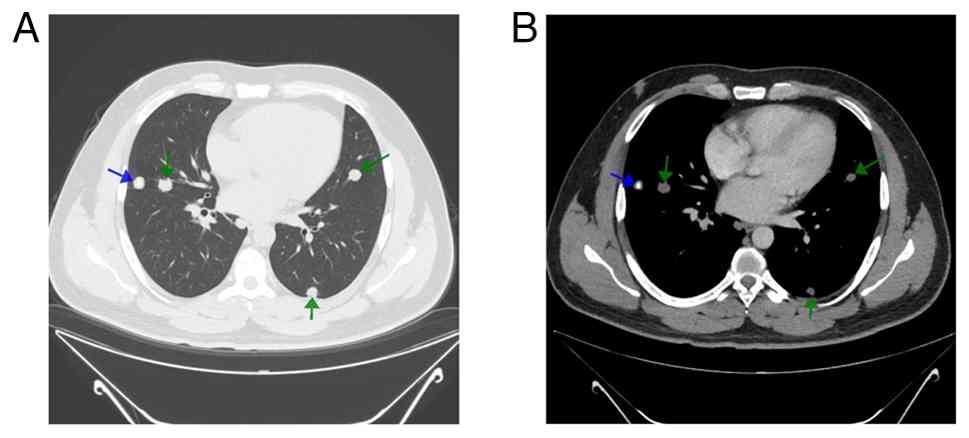

A contrast-enhanced chest CT scan demonstrated multiple well-defined pulmonary nodules scattered throughout both lungs (Fig. 1). The largest nodule, measuring 15 mm, was located in the right upper lobe. Some nodules exhibited central calcifications and variable post-contrast enhancement, with no cavitation observed. The patient underwent a CT-guided core needle biopsy. A histopathological examination was performed by the hospital laboratory as follows: The analysis was performed on 5-µm-thick, paraffin-embedded sections. The sections were stained with 10% neutral buffered formalin at room temperature for 24 h. They were then stained with hematoxylin and eosin (H&E; Bio Optica Co, Italy for 1-2 min at room temperature and examined under a light microscope (Leica Microsystems GmbH). The histopathological examination revealed benign alveolar tissue, skeletal muscle tissue and hyalinized material (data not shown). Although a few atypical cells were noted, the tissue sample was insufficient for a definitive diagnosis or proper immune staining assessment. The case was reviewed by a multidisciplinary team, which recommended a video-assisted thoracoscopic surgery (VATS) to obtain a biopsy for a more comprehensive evaluation.

Chest computed tomography scan with IV

contrast. (A) Lung window on high-resolution computed tomography.

(B) Soft tissue window with IV contrast illustrating multiple

bilateral pulmonary nodules (green arrows), one of them containing

central coarse calcification (blue arrow).

Figure 1

Chest computed tomography scan with IV contrast. (A) Lung window on high-resolution computed tomography. (B) Soft tissue window with IV contrast illustrating multiple bilateral pulmonary nodules (green arrows), one of them containing central coarse calcification (blue arrow).